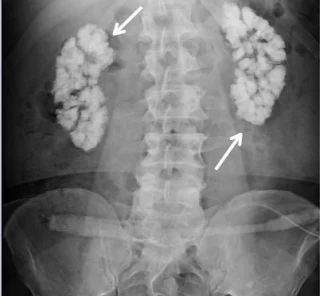

1. Intravenous Pyelography.

It is also called, Intravenous Urography and abbreviated as IVP. It is a radiographic examination of urinary tract including renal parenchyma calyx and pelvis after intravenous injection of contrast medium.